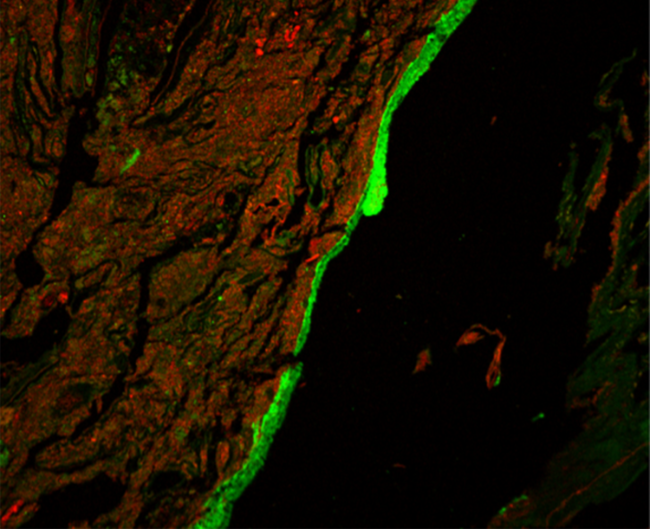

A research team led by Dr. Lijun Xia from the Oklahoma Medical Research Foundation developed an imaging method to visualize mucus production in the entire colons of mice. They examined O-glycosylated mucus production and its effects on gut bacteria in healthy mice and those with a disrupted microbiome.

The imaging showed that, contrary to current thinking, most gut mucus production happened in the proximal colon (the first and middle parts). Clumps of fecal matter and bacteria were coated with this mucus as they traveled through the colon. They then picked up a different type of mucus produced in the distal colon (the last part, closer to the rectum). Together, the two types of mucus encased the fecal pellets and largely kept bacteria from directly interacting with the tissue lining the colon.